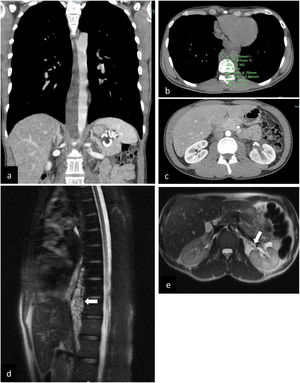

(a–c) (original images) – Whole-body CT – (a) coronal, contrast-enhanced (b) axial, unenhanced: prevertebral heterogeneous low-density (4 HU – fluid content) mass involving the thoracic aorta, from D6 to L1 (through diaphragm); (c) axial, contrast-enhanced: discrete heterogeneous density of retroperitoneal fat and central low attenuation areas in the left kidney; (d–e) (original mages) Chest-abdomen MRI – (d) MRI (sagittal): multiseptated serpiginous lesion in the posterior mediastinum/prevertebral (white arrow), forming a structure that molds to vascular structures (10.5cm in the craniocaudal diameter). (e) MRI (axial): left perirenal lesion molding to the renal hilum (white arrow), hyperintense on T2-weighted sequences, with multiloculated areas (equally hyperintense on T2).

We report the case of a 35-year-old man who presented in April 2021 with a 24-h history of nausea, vomiting, fever, and elevated inflammatory markers. He reported pleuritic pain with years of evolution. Chest posteroanterior radiograph was normal. Whole-body computed tomography (CT) showed a low-density prevertebral heterogeneous mass involving the descending thoracic aorta and extending to the retroperitoneal fat and left perirenal space (Fig. 1a–c). A diagnosis of aortitis was suggested, and the patient was admitted. The echocardiogram was normal.

Reviewing the CT images, it was possible to exclude the involvement of the aorta, since it was a mass of the posterior mediastinum that molded around the vascular structures without involving them. Lymphoproliferative disease, germ cell tumor and neurogenic tumor were considered the main possibilities.

Magnetic resonance imaging (MRI) was performed, showing a multiseptated serpiginous lesion in the posterior mediastinum/prevertebral, with a high signal on T2-weighted images, that molds to vascular structures. Additionally, there was a left perirenal lesion, T2-hyperintense, multiloculated, non-contrast-enhanced and unrestricted on diffusion sequences (Fig. 1d, e); adenopathy was not evident.

Upon reviewing the multiple exams, the most likely diagnostic hypothesis was incidental posterior mediastinal lymphangioma with extension to the perirenal region. A biopsy of the lesion was performed via endoscopic ultrasound. Flow cytometry of fine-needle aspiration was not compatible with lymphoma. The histology showed a benign vascular lesion with characteristics of lymphangioma, no signs of malignancy.